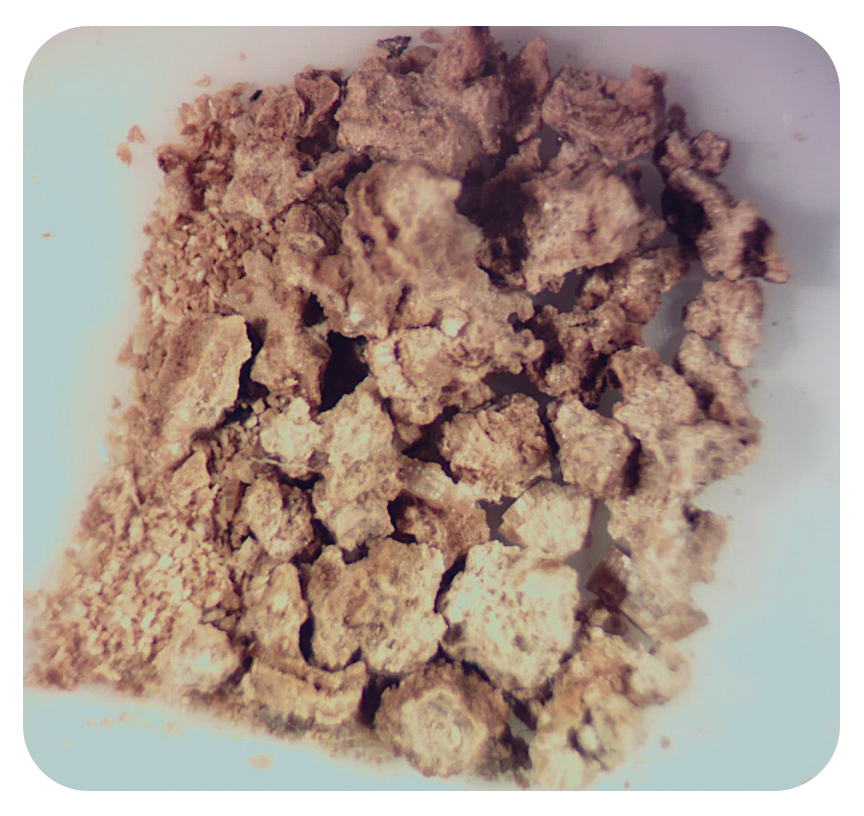

Специальный импульсный режим “UltraPulse” - фрагментация самых плотных камней на крупные фрагменты:

- высокая скорость фрагментации,

- эффективность соизмеримая с ультразвуковыми литотрипторами,

- снижение времени оперативного вмешательства,

- 100% stone free rate!

Специальный импульсный режим фрагментации «Ultra» моментально разрушает самые плотные камни на крупные фрагменты для последующей литоэкстракции.

Специальный импульсный режим “UltraPulse” - фрагментация самых плотных камней на крупные фрагменты:

- высокая скорость фрагментации, буквально пара импульсов может расколоть очень твердый камень на несколько фрагментов,

- эффективность соизмерима с ультразвуковыми литотрипторами,

- время оперативного вмешательства снижается,

- 100% stone free rate!